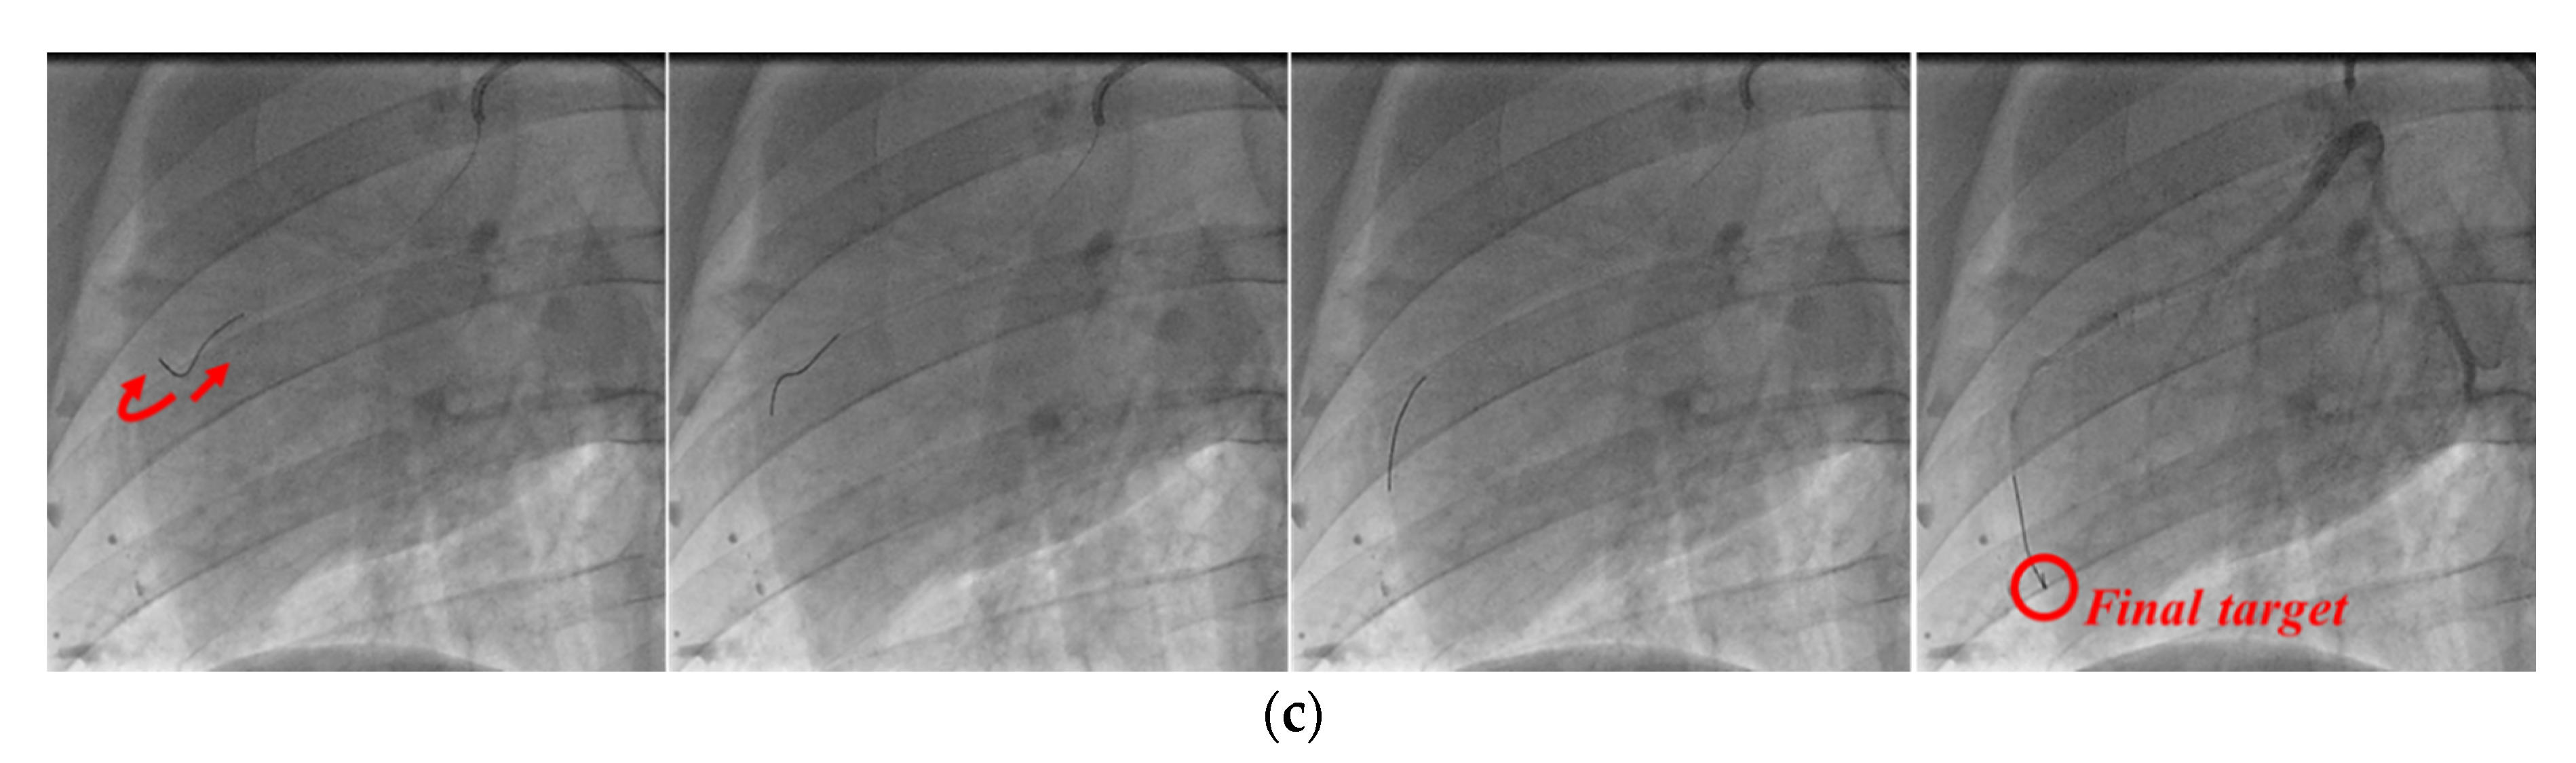

The angiography images of each stage in the process of guidewire advancement are shown in Figure 16. The guidewire was advanced, and it reached the first branch point, as shown in Figure 16a. Then, the guidewire was withdrawn from the first branch by moving it backward and rotating it, and it was advanced again to reach the second branch, as shown in Figure 16b. Finally, the guidewire was retracted and rotated again to exit from the second branch point, and then it was advanced to successfully reach the final target location, as shown in Figure 16c. In postoperative observation, the physician confirmed that there were no complications, such as perforation or bleeding.

Figure 16. Angiographic views of the right coronary artery of the pig. Process of inserting guidewire into (a) first branch, (b) second branch, and (c) final target.

Biosensors 11 00329 g016aBiosensors 11 00329 g016b